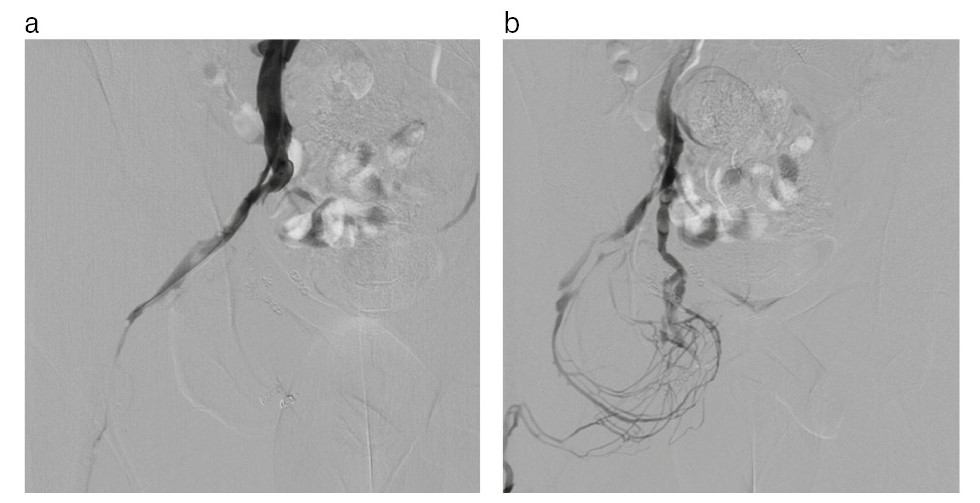

Инъекционный катетер в v. basilica по проводнику заменен на интродьюсер 5 Fr. На гидрофильном проводнике 260 см катетер perfoma hockey stick проведен в правую внутреннюю подвздошную вену, выполнена флебография в режиме цифровой субтракционной ангиографии (digital subtraction angiography – DSA), выявлен патологический дренаж контрастированной крови из системы дорсальных вен ПЧ (рис. 8).

Рис. 8. Флебограмма: а – правой общей подвздошной вены; b – части путей оттока из папапростатического сплетения.